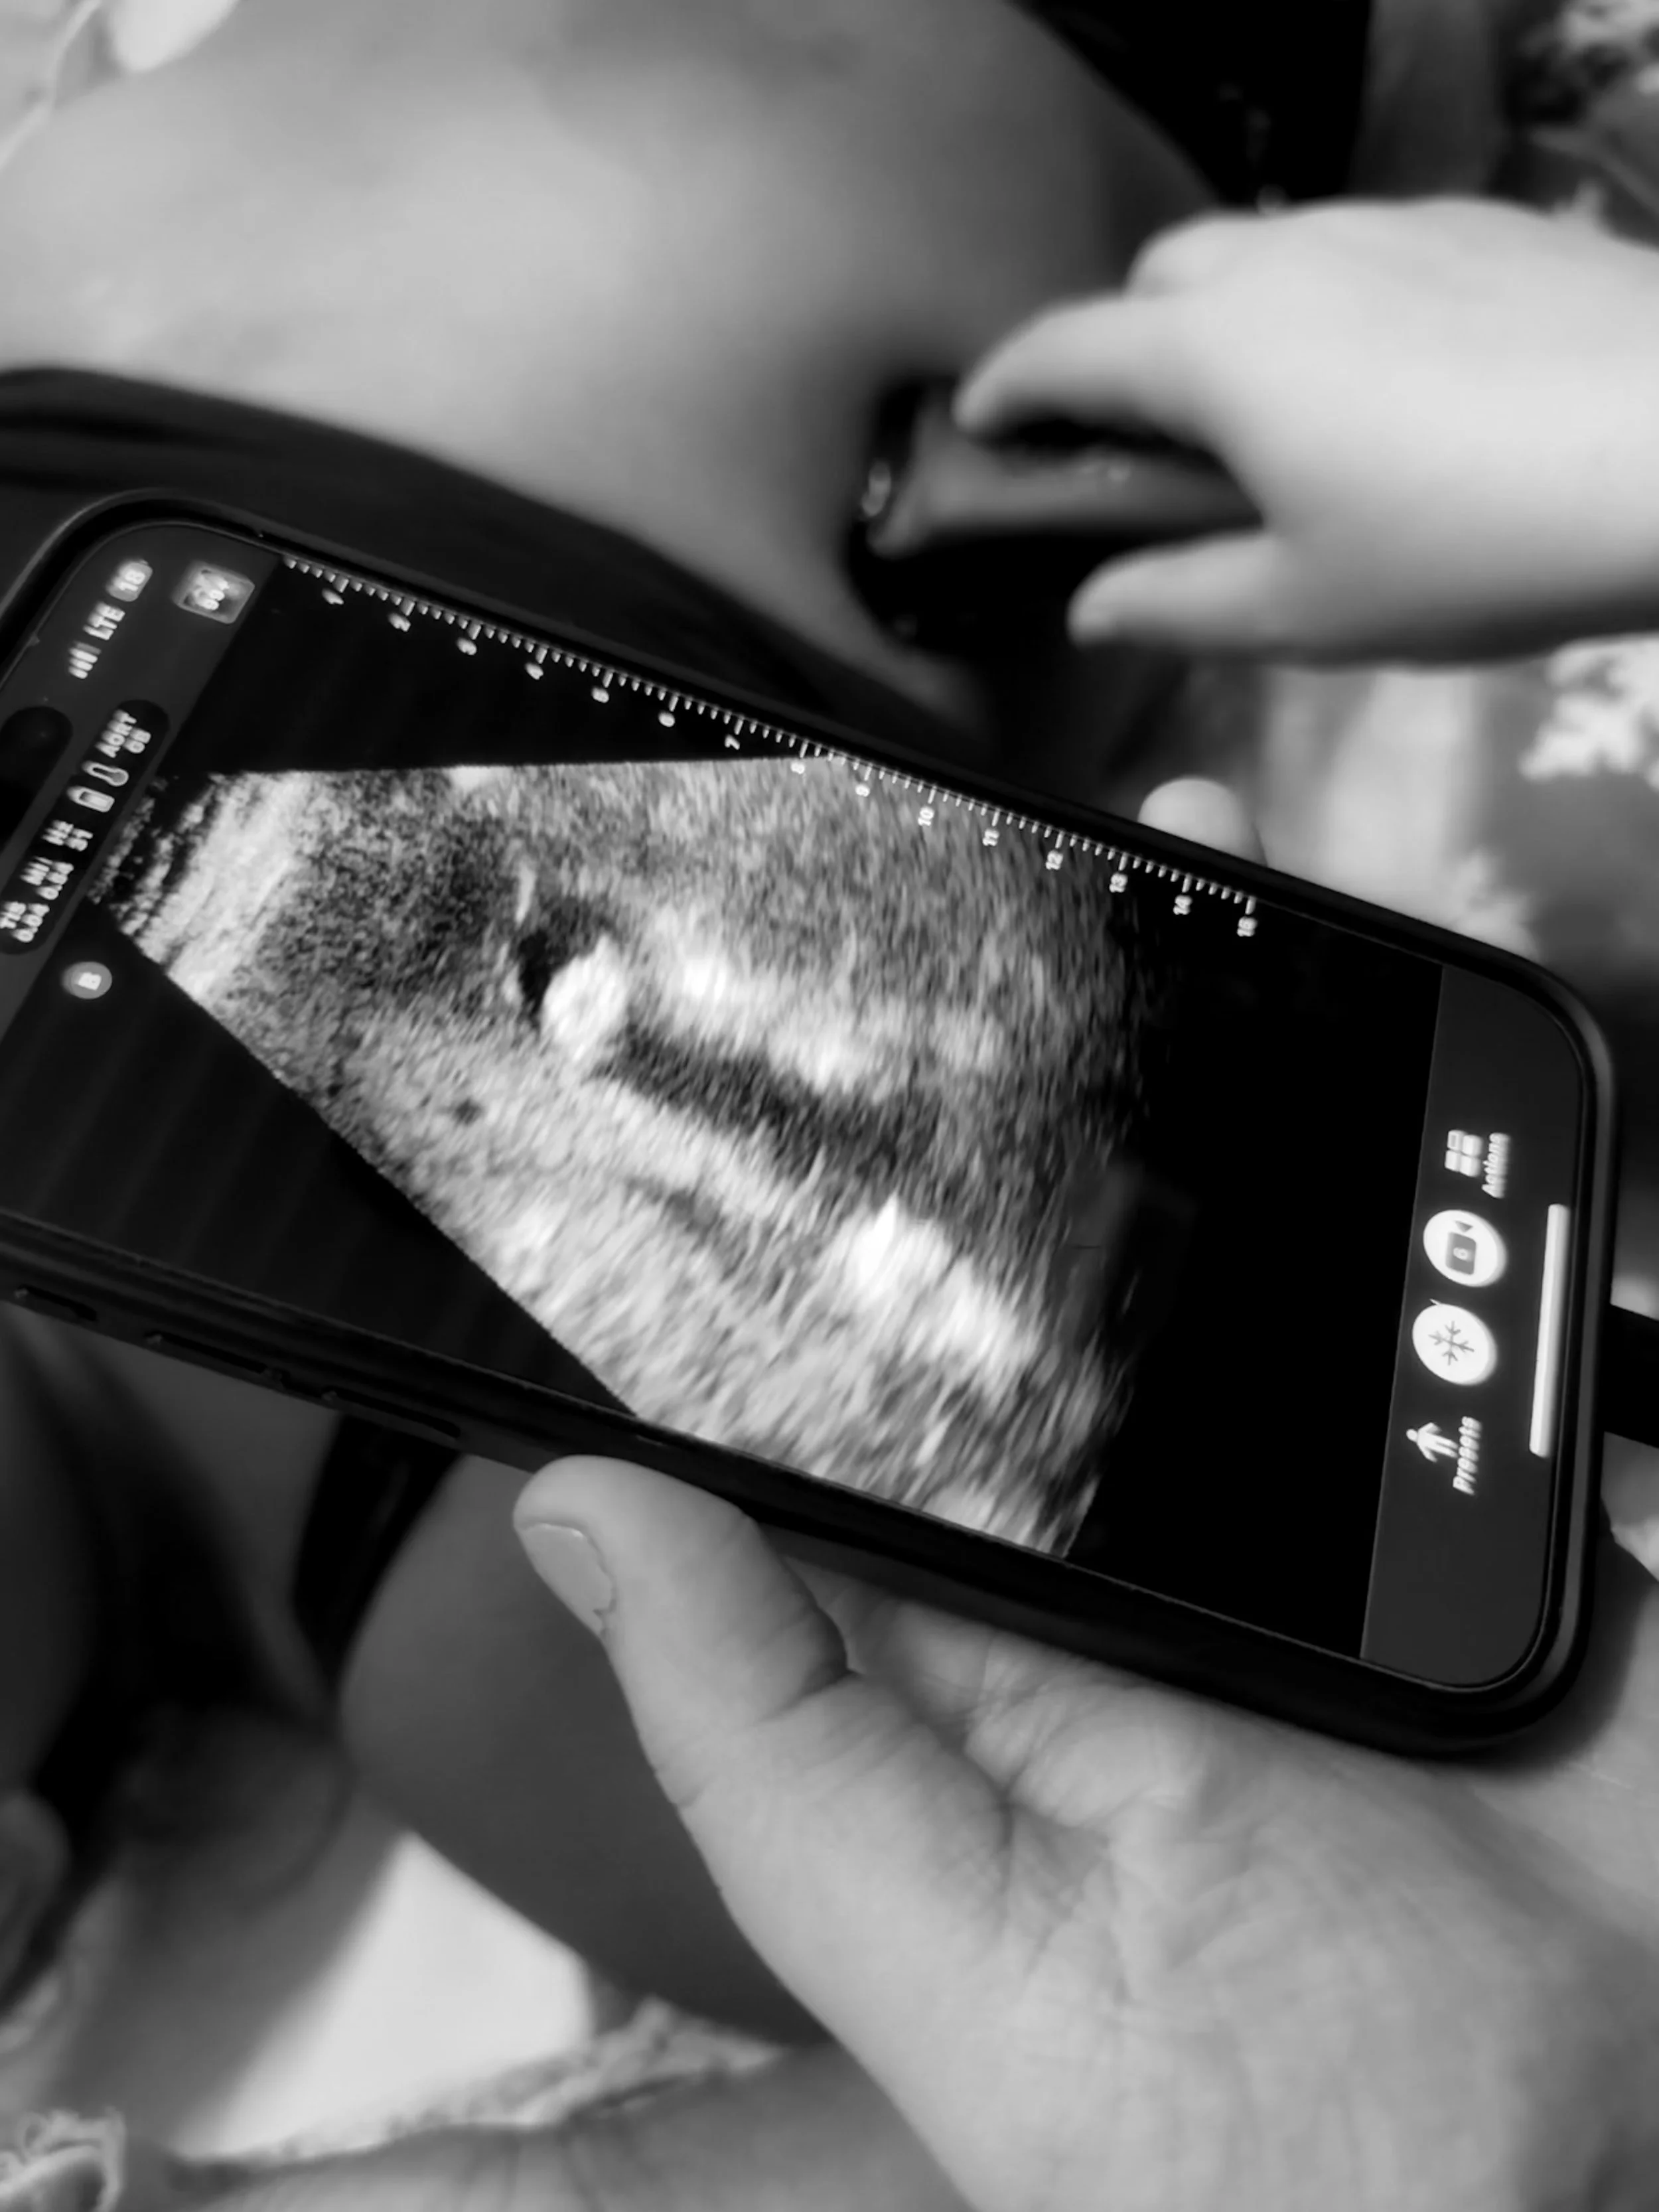

During a medical mission trip to Guatemala with Dr. Paat and Students for Medical Missions, I was part of a team that provided care to over 700 patients in underserved communities. One case left a lasting impression: a 32-year-old mother of three who presented with right upper quadrant pain radiating to her back. She described the pain as worsening after eating fish. Leading the encounter, my colleague translated as I took her medical history, performed a physical exam, and identified a positive Murphy’s sign. I applied skills recently learned in our lectures about the gastrointestinal system, recalling the population at greatest risk for having gallstones—female, of fertile age, and with an elevated BMI—and applying them in a real-world clinical setting.

As another colleague used a portable point-of-care ultrasound, I captured an image of the screen revealing a gallstone in the patient’s gallbladder. This confirmation of cholelithiasis validated her symptoms and guided her care, exemplifying the incredible utility of real-time imaging in resource-limited settings.

The portability and immediacy of the ultrasound device were invaluable. In a setting with limited access to healthcare, it provided instant visualization of pathology, enabling quick clinical decision-making and eliminating unnecessary delays. This moment underlined the significance of point-of-care ultrasounds, not just as a diagnostic tool, but as a means of empowering providers to deliver compassionate, effective care to those who need it most.